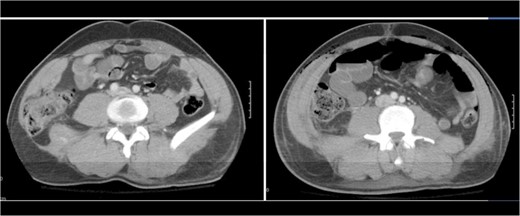

A 43-year-old male patient presented with a right-sided traumatic lumbar hernia after a blunt mechanism. The patient had been pinned between a dirt-mover’s claw arm resulting in a crush mechanism. He sustained injuries to the lumbar spine, sacrum, abdominal wall and 12th rib. On presentation, he did not have clinical or radiographic evidence necessitating abdominal exploration and was observed in a monitored setting. Computed tomography imaging demonstrated a Grynfeltt defect with herniation of the ascending colon and cecum through an area defined by the 12th rib, quadratus lumborum and internal oblique (Figures 1 and 2). After several days of observation and recuperation, the patient continued to have significant pain overlying the hernia site. We electively brought him to the operating room on post-injury Day 4. A laparoscopic repair of the traumatic hernia was performed. Key operative steps included: (i) Wide exposure of the hernia defect via incision of the peritoneum and transversalis as well as mobilization of the ascending colon and duodenal sweep (Figures 3 and 4). (ii) Primary repair of the defect with intra-corporeal suturing of the oblique musculature (Figures 5 and 6). (iii) Placement of an underlay mesh with appropriate redundancy at least 4 cm in all directions around the defect and seating against the iliac crest (Figure 7). Post-operative imaging demonstrates obliteration of the hernia defect and restoration of the abdominal wall (Figures 8 and 9). The patient has recovered, returned to the work force and has no pain or bulge at the repair site 6 months after injury.

With the patient in the left lateral decubitus the herniated right colon spontaneously reduces and the hernia is demonstrated.